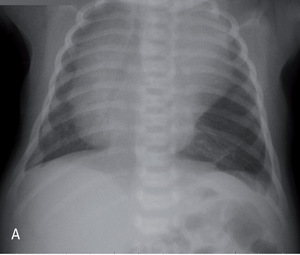

Rycina 2. Zdjęcia przeglądowe tylno-przednie (A) i boczne (B) dwutygodniowej dziewczynki z sekwestracją zewnątrzpłatową lewego płuca.